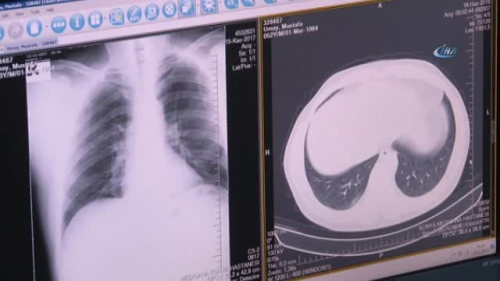

KONYA - Medicana Konya Hastanesi Göğüs Hastalıkları Uzmanı Gülfem Yıldırım, Türkiye'de ölümlerin en sık üçüncü nedeninin KOAH olduğunu söyledi. Göğüs Hastalıkları Uzmanı Gülfem Yıldırım, KOAH'ın sanıldığının aksine çok sık görüldüğünü ifade ederek, "KOAH, Kronik Obstrüktif Akciğer Hastalığının kısaltılmış tanımıdır. Açılımından anlaşılacağı gibi kronik ve obsesyonla seyreden akciğerlerin hasarlanmış olduğu bir hastalıktır. Sanıldığının aksine çok sık görülmekle beraber Türkiye'de ölümlerin en sık üçüncü nedenidir. 40 yaş üstü hastalarda yüzde 15-20 oranında gözükmektedir. KOAH'a en sık yol açan etmenler başta sigaradır. Sigara içenlerde KOAH sıklığı 10 kat daha fazla gözükmektedir. Bunun yanında tütün kullanımının diğer yolları nargile, pipo gibi sebeplerden dolayı da KOAH sıklığı artmaktadır. Bunun dışında mesleki etmenler, kimyasal maddelere maruz kalma gibi etmenler ve İç Anadolu'da çok sık görülen yemek pişirmede kullanılan ısınmada odun, tezek gibi yakıtların kullanılması KOAH sıklığının artmasındaki en sık etmenlerdir" dedi. "KOAH tanısını koymak için öncelikle hastanın kendisinden şüphe etmesi gerekir" KOAH tanısını koymak için öncelikle hastanın kendisinden şüphe etmesi gerektiğini söyleyen Uzman Doktor Gülfem Yıldırım, "Nasıl şüphe edelim kendimizden? Eğer 40 yaşın üstündeysek, nefes darlığımız oluyorsa, uzun süredir sigara kullanıyorsak, öksürük ve balgam gibi şikayetlerimiz varsa öncelikle şüphelenmemiz gerekir. Tanı koymak için bir göğüs hastalıkları uzmanına başvurmamız lazım. Göğüs hastalıkları uzmanı da bir solunum fonksiyon testiyle halk arasında nefes ölçümü denilen testle biz tanıyı koyabiliyoruz. KOAH'ta tedavide iki ana amacımız vardır. Birincisi hastalığın şikayetlerini azaltmak, hastadaki bulguları azaltmak. Bunun için kullanacağımız nefes yoluyla alacağımız bazı ilaçlar vardır. Eğer çok ağır KOAH hastasıyla oksijen tedavisi gibi evde uyguladığımız tedaviler vardır. Bunun dışında hastalığın ilerlemesini engellemek için mutlaka risk faktörlerinden uzak tutmak en önemlisi sigarayı bırakmak gerekir. KOAH hastalarının öncelikle en kısa sürede sigara içiyorlarsa sigarayı bırakmaları gerekir. Diğer çeşitli risk faktörlerinden de uzak durmaları gerekir. Bunun dışında düzenli doktor kontrollerini yapmalılar. Doktor kontrollerinde ilaçlarının düzenli olarak ayarlanması yine doğru ilaç kullanımının kontrol edilmesi gerekir. Hastaların mutlaka sonbahar aylarında grip aşılarının yılda bir kez yapılması ve ömürde bir kez zatürre aşısı dediğimiz aşının yapılması gerekir. Yine bu hastaların beslenmelerine dikkat etmeleri gerekir. Vücut dirençlerini düşürmemeleri için sağlıklı, dengeli beslenmeleri gerekir. Düzenli yürüyüş hafif egzersizlerle vücut direncini kontrol altında tutmaları gerekmektedir" ifadelerini kullandı.